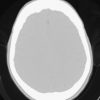

Mỡ nội sọ

Mỡ nội sọ - Ảnh 4

» Thông tin: Nam giới – 46 tuổi.

» Lâm sàng: Kiểm tra sức khỏe.